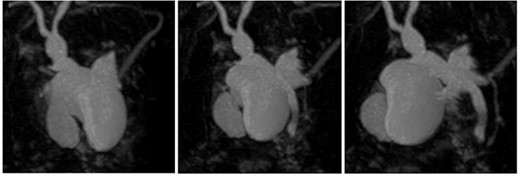

3D reconstruction of duplicated gallbladder and biliary tree from MRCP.

Subsequent review of preoperative imaging solved the mystery. Duplicated gallbladder with double cystic ducts was clearly evident on CT and magnetic resonance imaging (MRI) which were hidden in plain sight (Figs 4–7). CT cholangiogram (Fig. 3) was performed Day 1 post-operatively showing the double cystic duct with no evidence of bile leak. Rest of patient’s admission was uneventful and he was cleared for discharge on Day 5 post-operatively. Patient remains well and was back to his daily activities during his follow-up review.

Anatomical anomalies of the gallbladders and its ducts have been documented from as early as 1926 by Edward Boyden [11]. Autopsy studies by Boyden reported that double gallbladders occur in 0.03% of cases [11]. To date, there have been 62 cases of patients with double gallbladder reported since 1926, including our case [3–9]. Duplicated gallbladders can be classified into three types using Harlaftis Classification: Type I where double gallbladder drains into CBD via one cystic duct, Type II where two separate cystic ducts drain into CBD, and Type III where gallbladder is separated and has duplicated cystic ducts or have triple gallbladder [4]. Given the preoperative MRCP and postoperative CT cholangiogram findings, our case is a Type II accessory gallbladder with ‘H’ duplication.